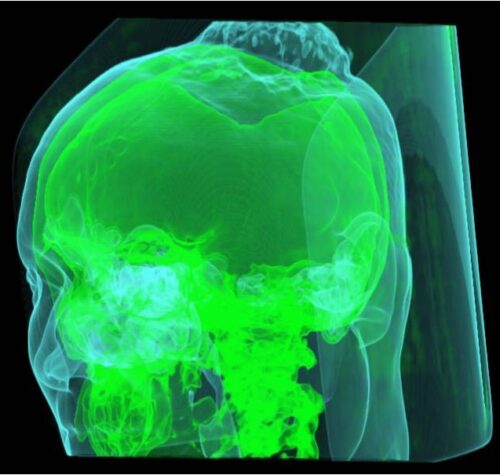

I suoi quattro figli hanno dato il consenso alla donazione senza esitazione: una donna di 82 anni di Canosa ha donato il fegato prelevato dalla equipe del Policlinico di Bari….